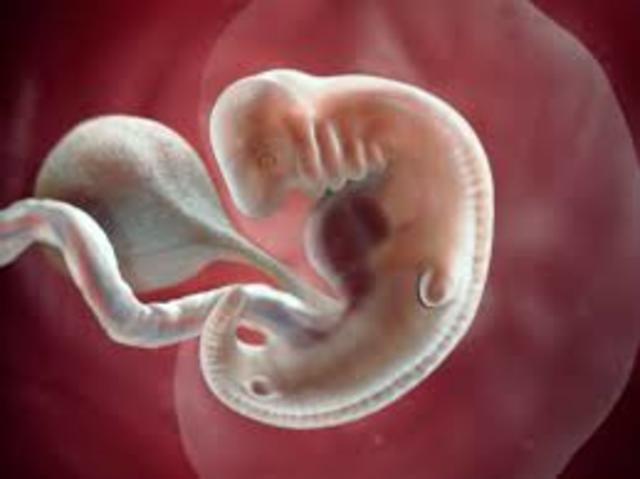

Embryo- A unborn offspring in the process of development, during the period from approximately the second to the eighth week after fertilization.

• 2nd Month

2nd Month

6 weeks:

1. 5/8 inches long.

2. Eyelids form.

3. All organs developed.

8 weeks:

1. Bones and muscles developing.

2. Leg buds start to grow.

3. Arm buds start to grow.